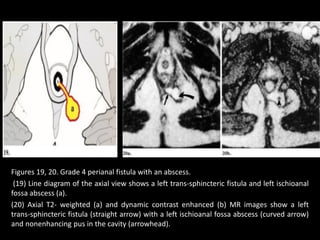

Grade 4:

• Grade 4: Trans-sphincteric Fistula with Abscess or Secondary Track

within the Ischiorectal Fossa.—

• A trans-sphincteric fistula can be complicated by sepsis in the

ischiorectal or ischioanal fossa (Figs 17, 18).

• Such an abscess may manifest as an expansion along the primary

track or as a structure distorting or filling the ischiorectal fossa.

• Axial and coronal dynamic contrast-enhanced MR imaging clearly

depicts a trans-sphincteric abscess, which characteristically has a

central focus of low-signal-intensity pus (Figs 18–20).

Figures 19, 20. Grade 4 perianal fistula with an abscess.

(19) Line diagram of the axial view shows a left trans-sphincteric fistula and left ischioanal

fossa abscess (a).

(20) Axial T2- weighted (a) and dynamic contrast enhanced (b) MR images show a left

trans-sphincteric fistula (straight arrow) with a left ischioanal fossa abscess (curved arrow)

and nonenhancing pus in the cavity (arrowhead).

Figures 19, 20.Grade 4 perianal fistula with an abscess. (19) Line diagram of the axial view shows a left trans-sphincteric fistula and left ischioanal fossa abscess (a). (20) Axial T2- weighted (a) and dynamic contrast enhanced (b) MR images show a left trans-sphincteric fistula (straight arrow) with a left ischioanal fossa abscess (curved arrow) and nonenhancing pus in the cavity (arrowhead).